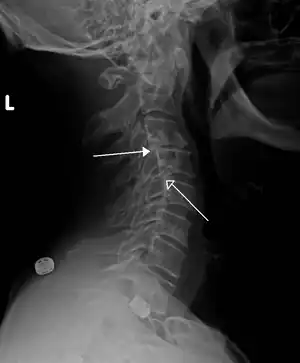

| X-ray of the lateral lumbar spine with a grade III anterolisthesis at the L5-S1 level. | |